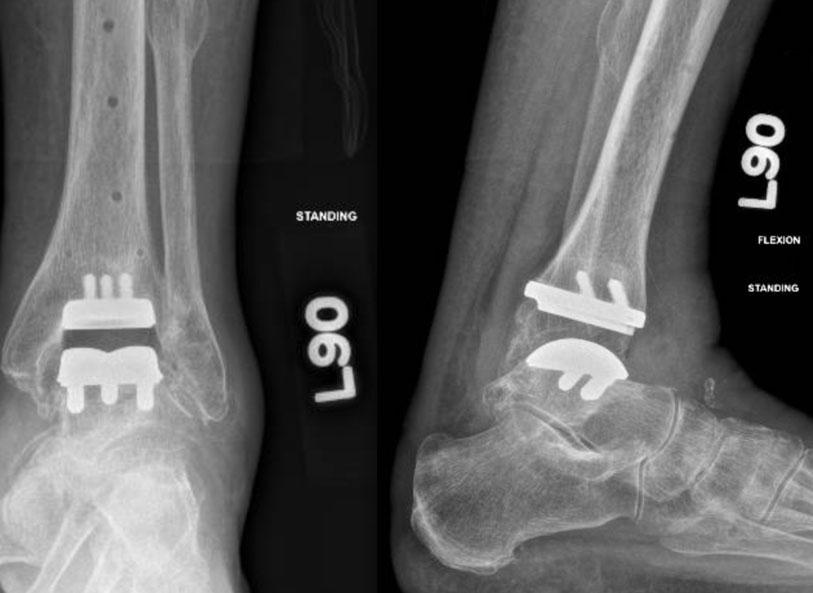

X-rays after ankle replacement

CT Scan-based Cutting Guides Ensure More Accuracy

A major advancement in total ankle replacement involves the use of CT scan-based cutting guides. These guides, which are customized to each patient, ensure that surgeons make more accurate bone cuts. This, in turn, provides an additional method to improve intraoperative alignment.

Traditionally, CT-based cutting guides have not been widely used, even in hip and knee replacement surgeries. However, by using this technology, surgeons may reference the bony anatomy as precisely as possible. Park says, “The custom cutting guides allow for optimization of the alignment for both the tibial and talar bone cuts. The process is incredibly accurate and helps us provide the best outcomes possible.”

While total ankle replacements may be susceptible to the same risks as other joint replacement procedures, such as infection, malalignment, fractures, and wound complications, this patient recovered well from both total ankle replacements. She showed significant improvement in both gait and activity level following the bilateral joint surgery. Park agrees that her outcome was exceptional, saying, “This is one of the most rewarding surgeries performed in orthopedics for pain relief and quality of life. Full recovery can take up to a year, but in properly selected patients, this procedure can be life-changing.”